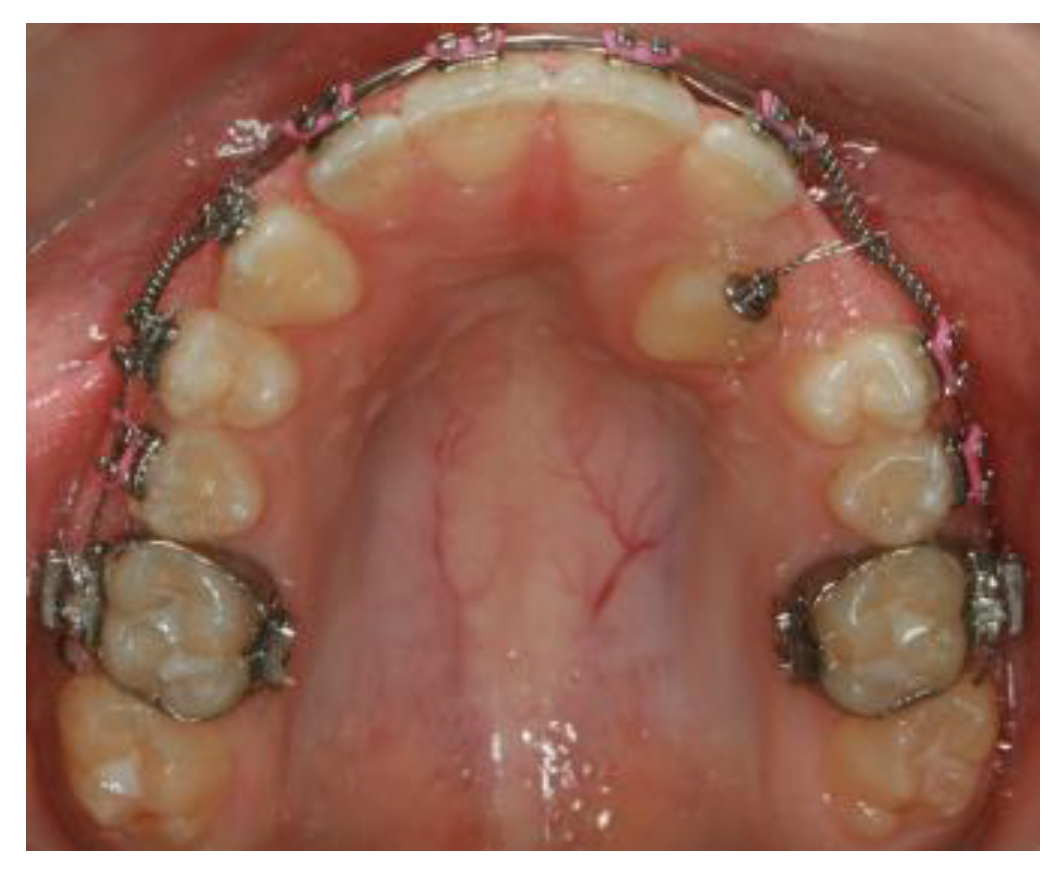

In the CG, the bonded bracket on the impacted maxillary canine was attached to the 0.019 × 0.025-inch NiTi wire inserted into the other upper brackets with the long stainless steel ligature wire. This long ligature was activated approximately every three weeks to track the impacted maxillary canine into the dental arch (Figure 4).

Figure 4. The 0.019 × 0.025-inch NiTi wire was inserted into the brackets on the aligned maxillary teeth to stabilize them, and the long stainless steel ligature was attached to the impacted maxillary canine with a bonded bracket.